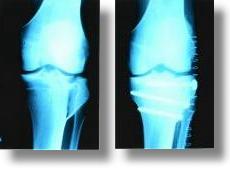

| Rheumaorthopädie |

Entzündlich rheumatische Krankheiten spielen sich vornehmlich an den

Gelenken ab. Neben einer medikamentösen Therapie sind in erster Linie

orthopädische Maßnahmen mit lokalen Injektionsbehandlungen, physikalischer

Therapie, orthopädischen Hilfsmitteln und orthopädischer Chirurgie

notwendig. Der Orthopäde arbeitet hierzu eng mit dem internistischen

Rheumatologen zusammen. |